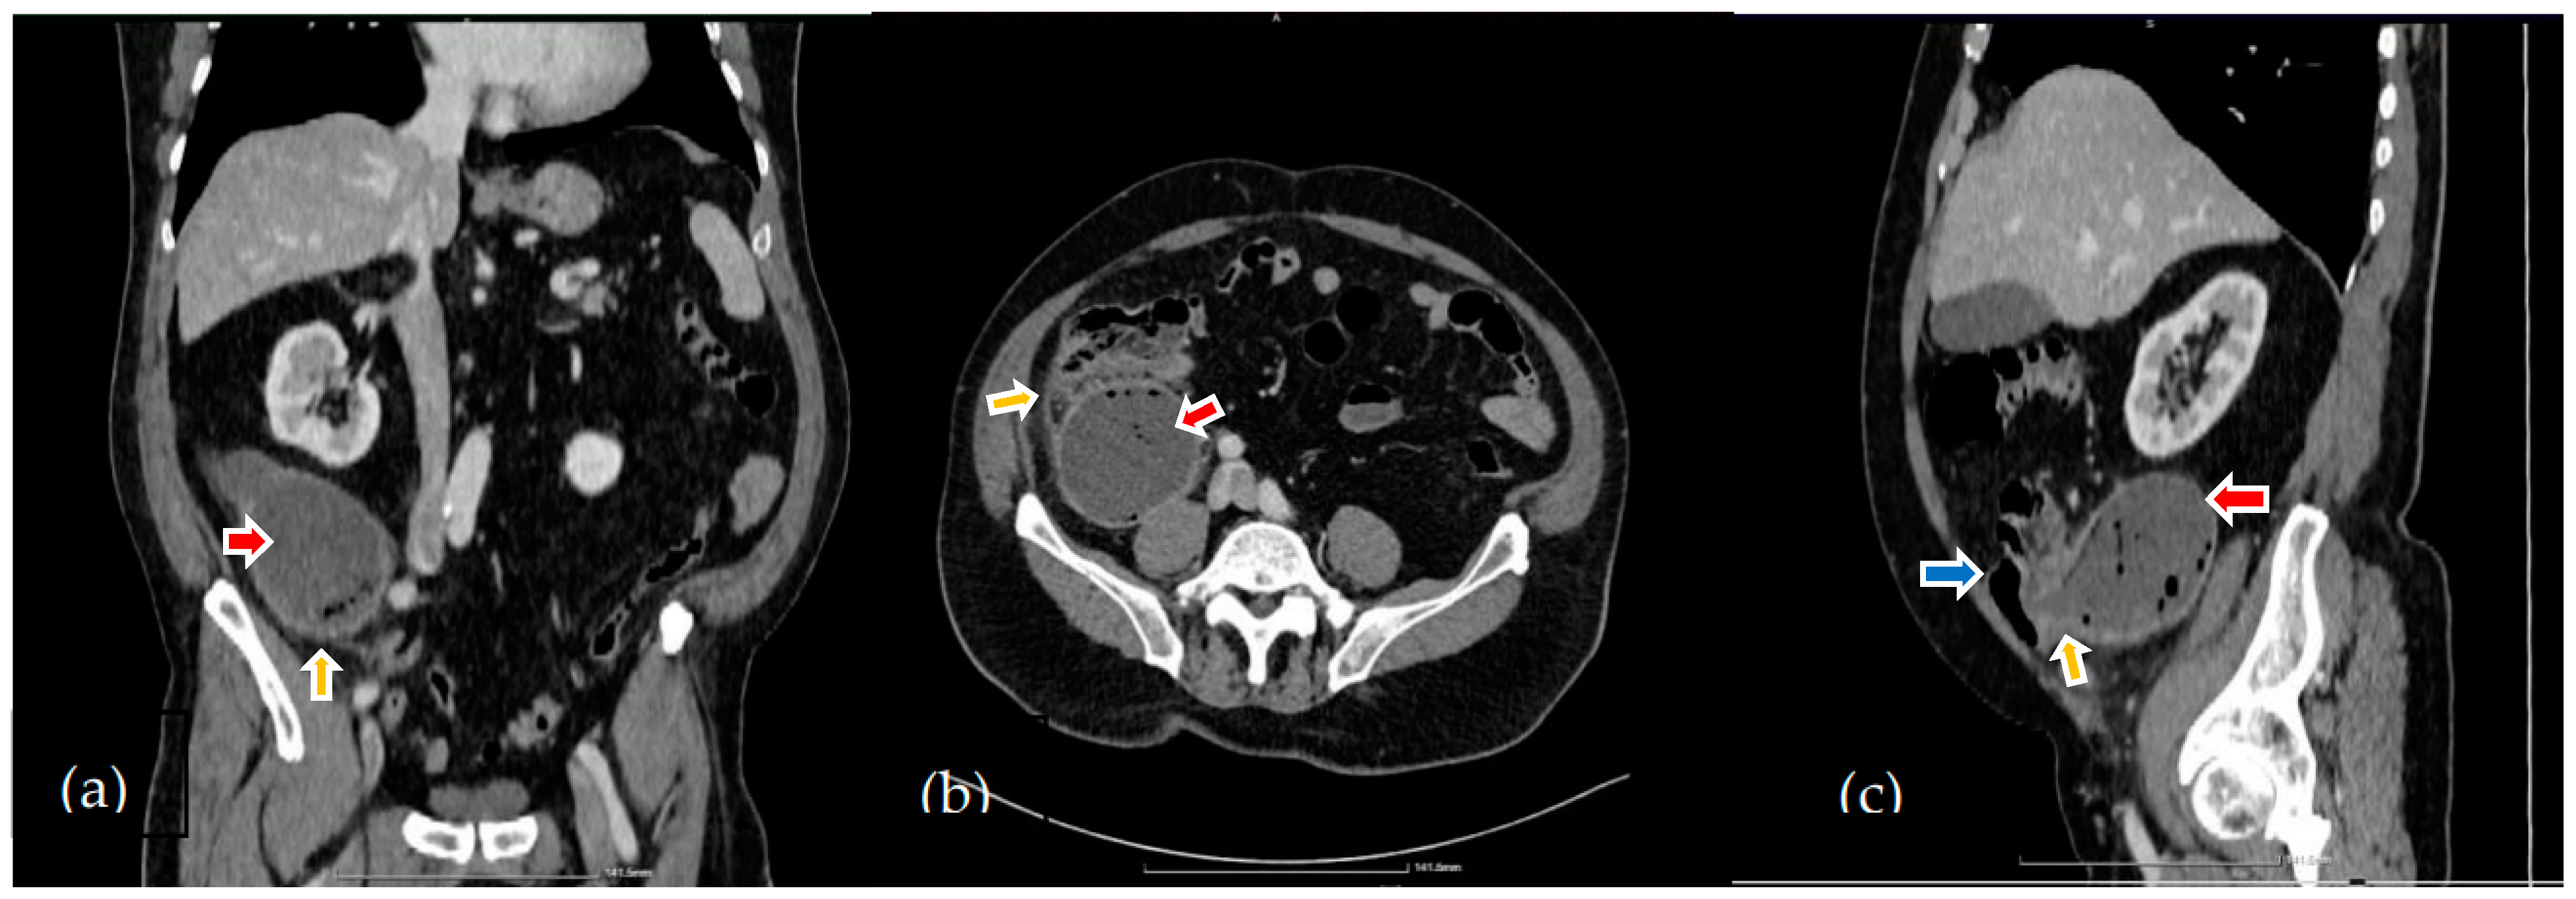

2. Case Report